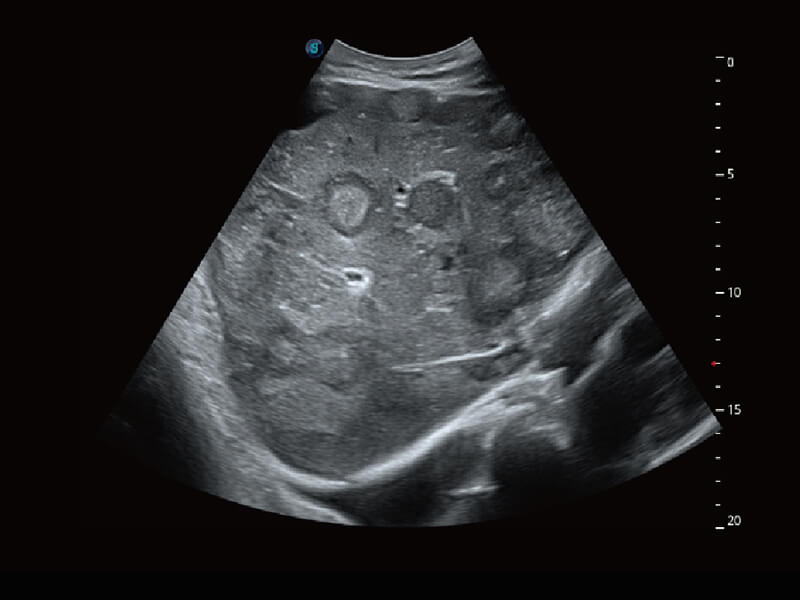

成像功能

S60探头工艺,从前端信号处理每一个环节采集无损声学数据,真实还原组织原貌,再现解剖细节。